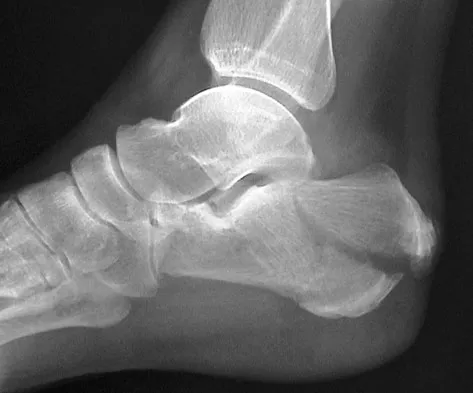

Figures 38a and 38b show the CT scans of a 64-year-old woman. What is the most likely diagnosis?

Explanation

The CT scans show large cystic lesions in the talus and calcaneus with complete subluxation of the subtalar joint, allowing the calcaneus to slide laterally until it becomes blocked by the fibula. The cause of this subluxation is severe posterior tibial tendon dysfunction. Although no fibular fracture has yet appeared, it can occur with continued stress from the calcaneus. There is, however, a pathologic fracture in the medial calcaneus through a medial degenerative cyst. The joint space is irregular and not symmetrical as would be seen in an inflammatory arthropathy. Cystic lesions are not present in the tibia. No stress fracture is seen in the talus. Coughlin MJ: Sesamoids and accessory bones of the foot, in Coughlin MJ, Mann RA (eds): Surgery of the Foot and Ankle, ed 7. St Louis, MO, Mosby, 1999, pp 437-499.